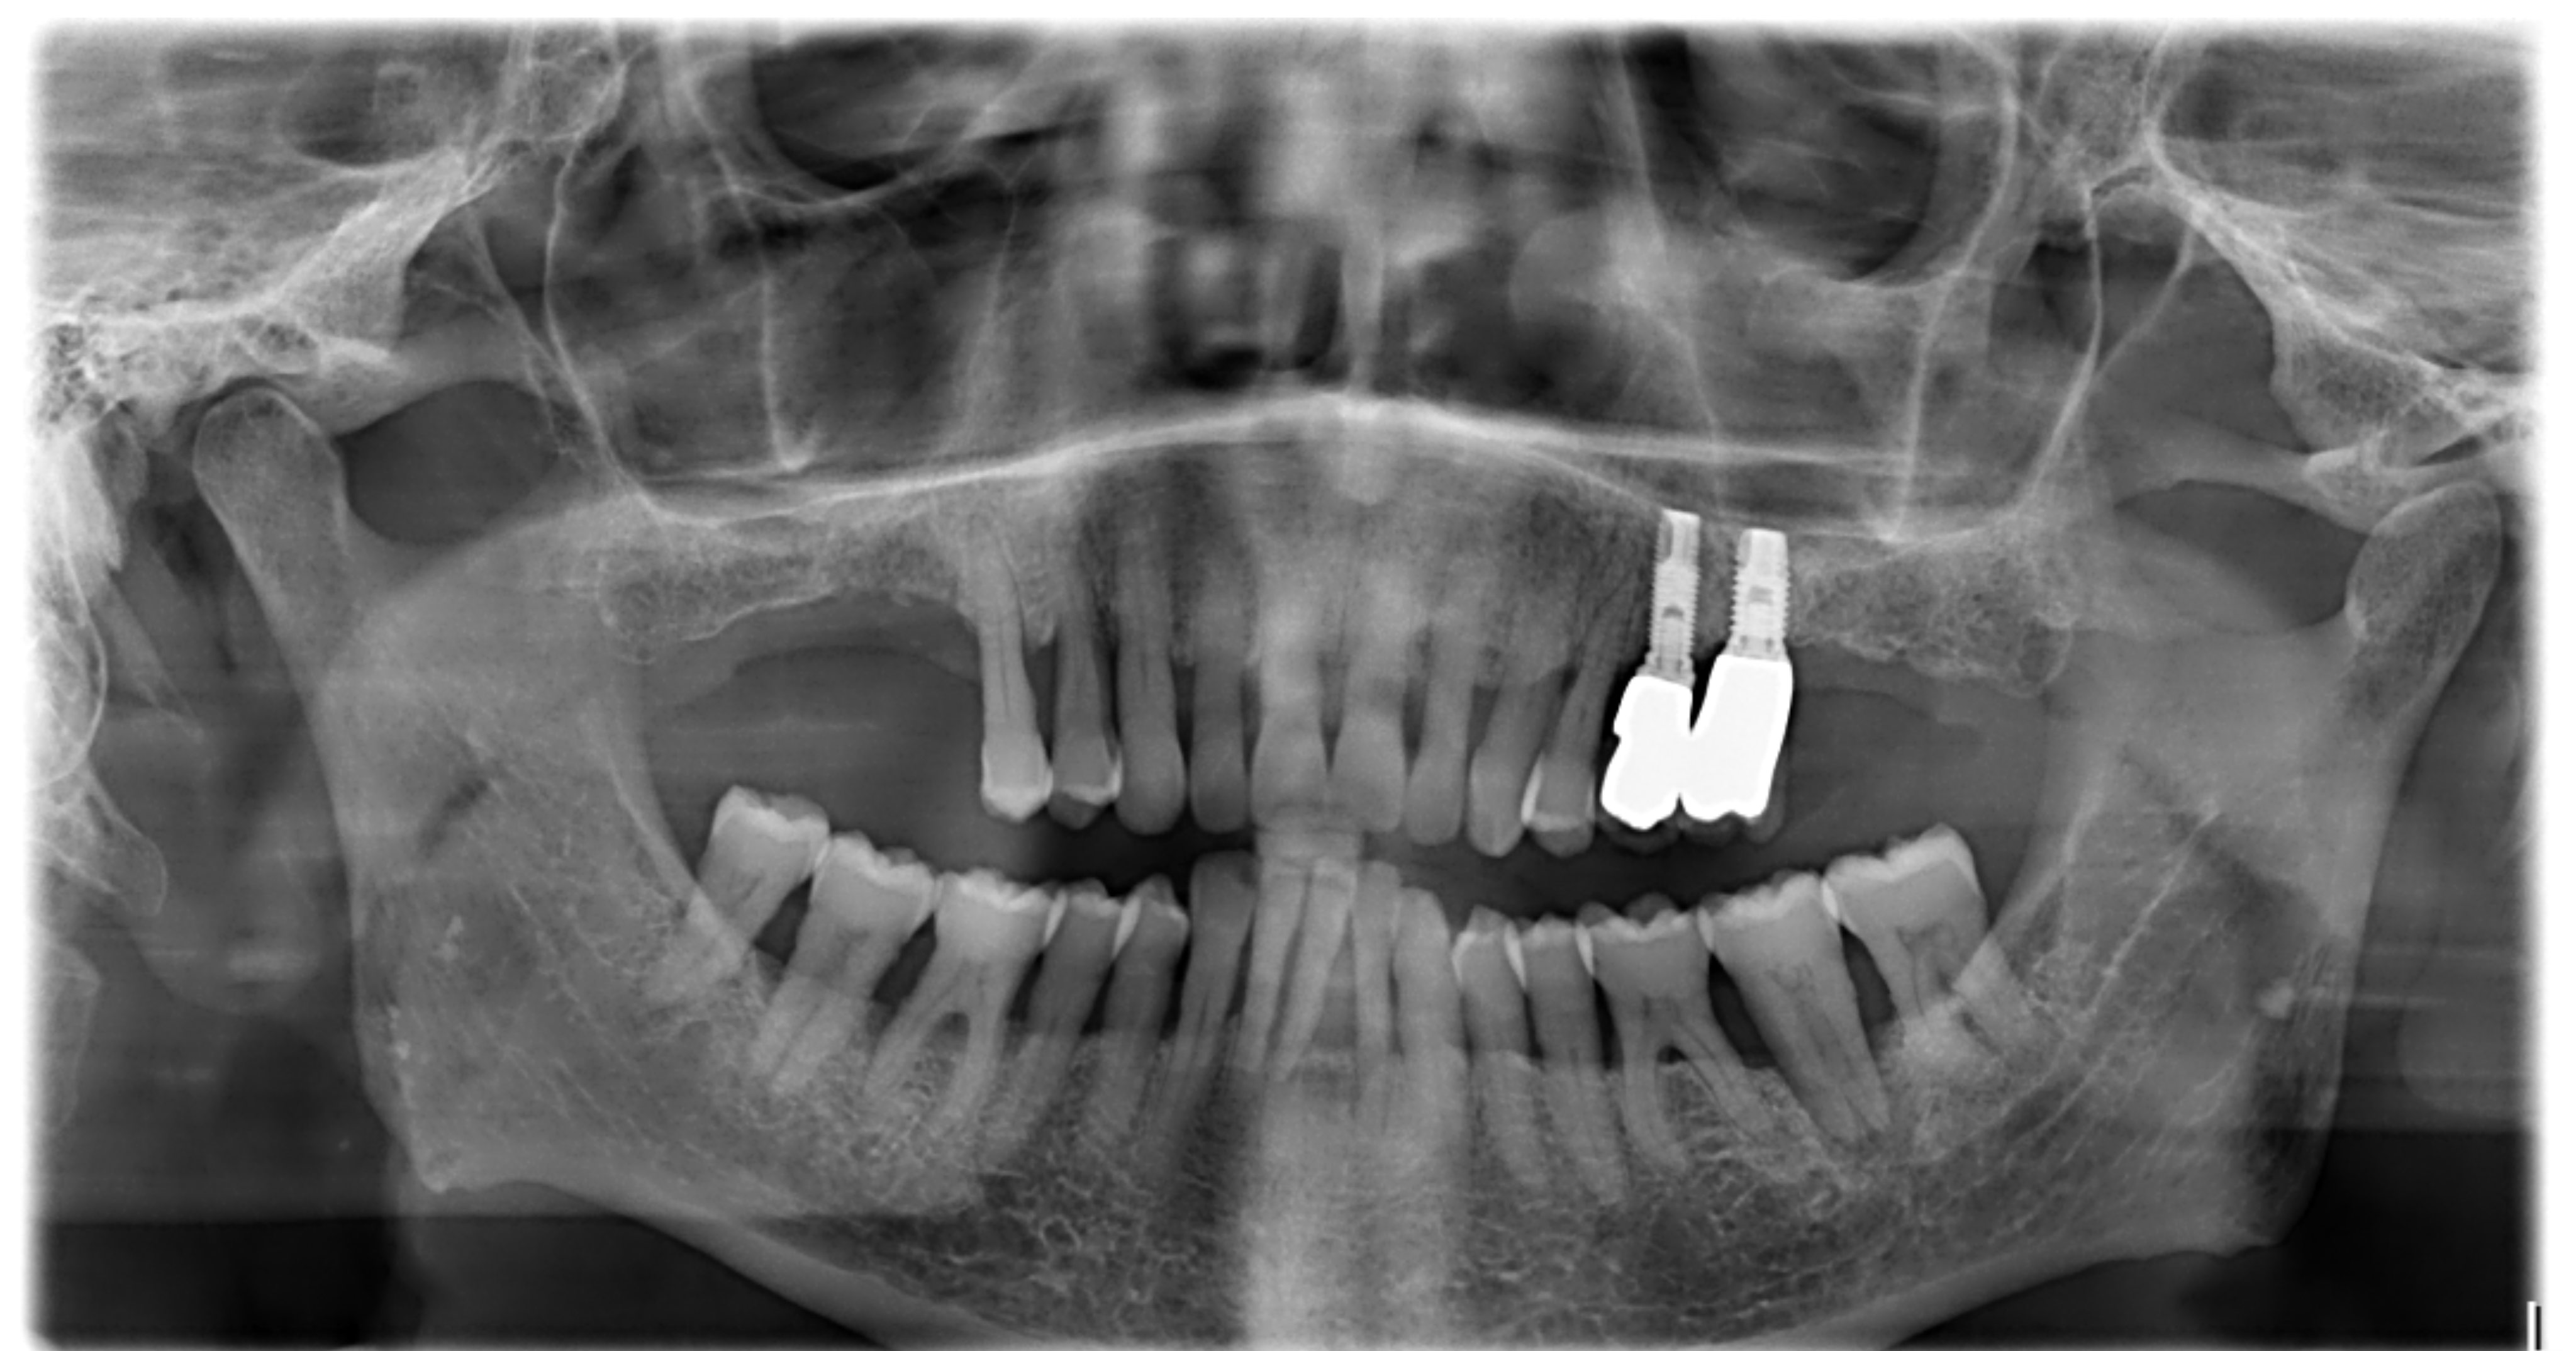

Je voudrais avoir vos avis sur cas que j'ai récemment eu au cabinet. Il s'agit d'un patient de 75 ans, atteint de la maladie d'Alzheimer. Une implanto lui a posé les 2 implants qu'il a en position de 24.25 avant de lui proposer d'entamer un traitement paro quand la 31 est tombée toute seule...

Sérieusement, un traitement paro sur un Alzheimer (!!!) alors que si cela se trouve les implants 16 17 ainsi que 27 peuvent être poser sans sinus lift.

37 semble condannée et 46 pas bien partie non plus.

Pour Vernal, en ce qui concerne la pose d’implant pour remplacer les dents manquantes, mieux vaudrait ne pas se lancer s’il y a une parodontite non traitée non ? Il n’existe pas un risque de dissémination aux autres sites ?

Y a des implantos qui n’ont vraiment peur de rien. Poser des implants dans un contexte paro comme celui ci... c’est... couillu !

C'est pas couillu c'est foutage de gueule surtout! Je traite pas la paro rien a battre je plante 2clous, dans 6 mois 2 sur le scteur 10.